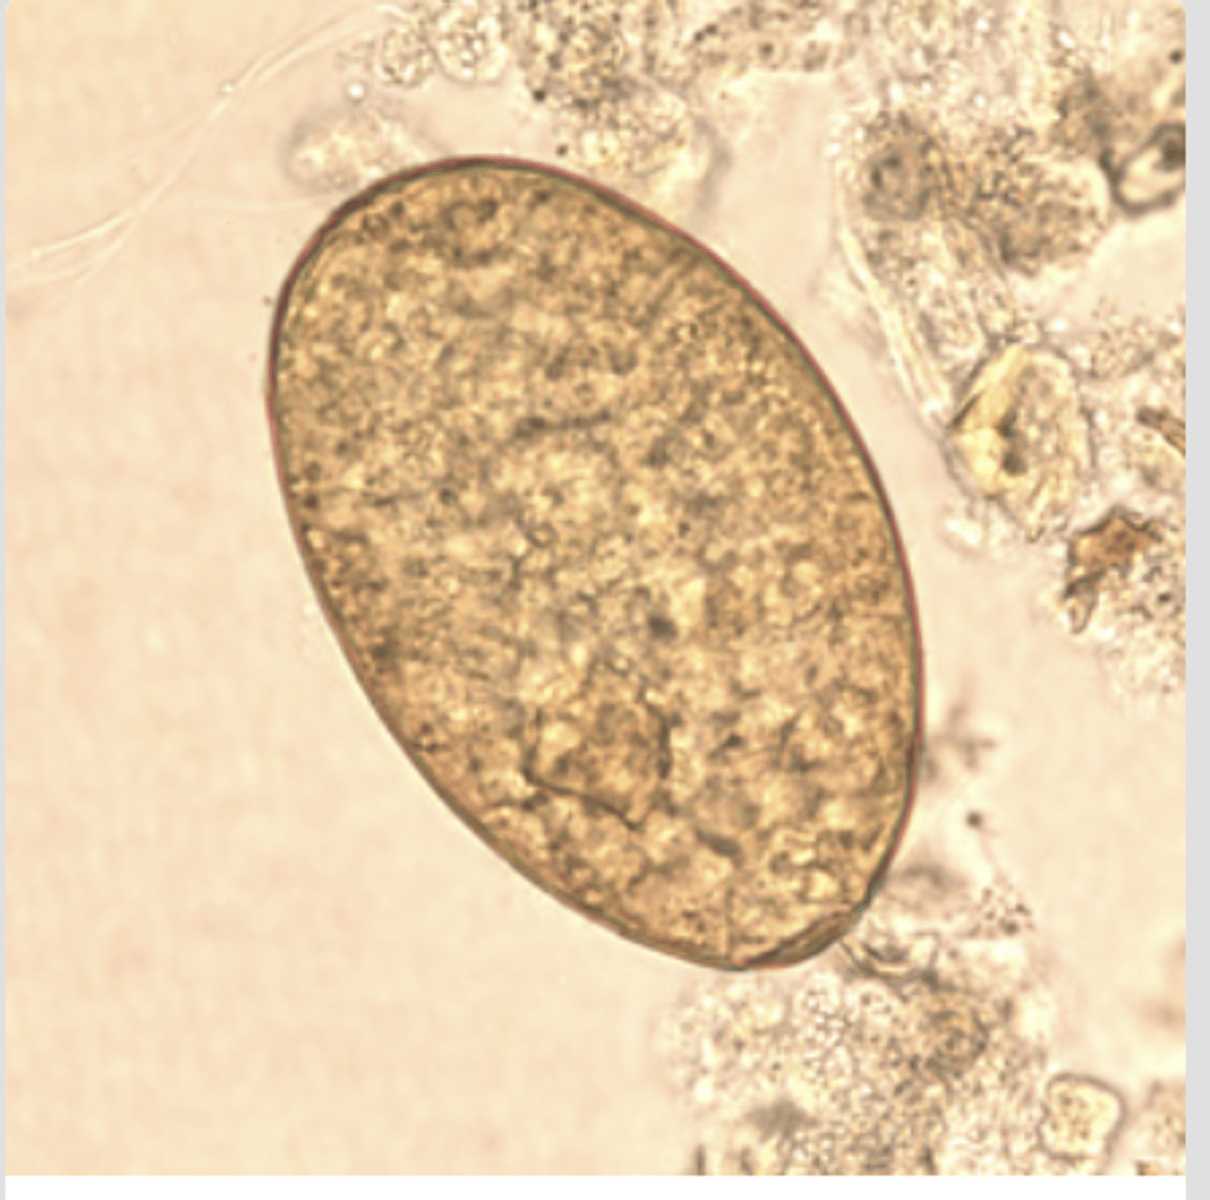

Fasciola hepatica/Fasciolopsis buski